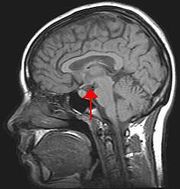

Hypothalamus

Hypothalamus (původní český název je podhrbolí, slovensky se někdy nazývá podlôžko) je částí mezimozku (diencephalon). Jeho činnost spočívá hlavně ve slaďování jednotlivých vnitřních orgánů do komplexní odpovědi. Například připravuje všechny orgánové soustavy na zvýšenou fyzickou, nebo psychickou zátěž.

Hypothalamus vytváří přední stěnu a dno III. mozkové komory. Od thalamu ho odděluje sulcus hypothalamicus. V hypothalamu bylo popsáno 22 jader. Klasickou klasifikací se stalo dělení podle Le Gros-Clarka, kterým se řídí i členění podle Nomina Anatomica (1977).